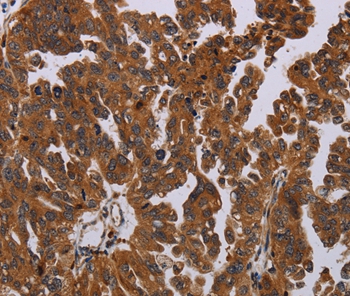

Immunohistochemical analysis of paraffin-embedded Human ovarian cancer tissue using #37794 at dilution 1/50.